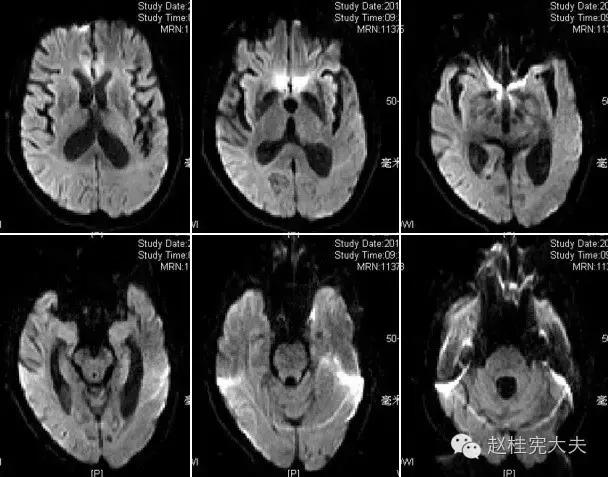

完善检查,头颅MRI回报:左侧颞顶枕叶急性梗死灶。

患者的磁共振影像不符合脑血管病的血供分布,跨了大脑中动脉和大脑后动脉范围,且病灶偏皮层分布。大脑前、中、后动脉血供分布(横断面)见下图

这不是一个真的“脑卒中”,而是一个“卒中样发作”。

上周,于发病后2月复查磁共振:

到此为止,MELAS的诊断应该在没有基因确诊的情况下在临床上得到认可了,患者明确诊断为线粒体脑肌病伴乳酸血症和卒中样发作(MELAS),解释了患者的所有症状,患者母亲不明原因地死亡也得以真相大白,患者的相关亲属们在未来的人生路上也多了一份呵护......